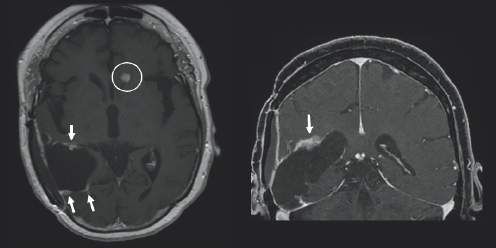

Light gray color variations are surrounded by black space and a white outline. On the top right of the image, near the midline, there is a white blob highlighted by a white circle. (Right) Charcoal gray color variations are surrounded by black space and a light gray outline.

FIGURE 3.4 Brain MRI after surgery. Follow-up axial (left) and coronal (right) post-contrast images, obtained 39 months follow-up, show progressive increased size of an abnormal ependymal enhancing nodule in the left frontal horn (white circle) that appears bright after being injected with IV contrast, consistent with a recurrent tumor.

A month after her surgery, Janet began chemotherapy and radiation treatment. She began trialing different chemotherapy drugs recommended by her team of physicians to pinpoint which would be most effective for her tumor. She was unable to be treated with the standard-of-care drug, TMZ, due to a severe anaphylactic allergic reaction. Despite desensitization to try to ween her on TMZ use, she continued treatment with lomustine, a different chemotherapy drug. Janet was placed on multiple clinical trials starting with the Belinostat/MRSI (magnetic resonance spectroscopic imaging) study and later the 5-ALA (5-aminolevulinic acid) study. Early on in her treatment, Janet turned to tumor treating fields (TTFs), to see if that form of treatment could provide her the benefit of tumor reduction. TTFs are commonly used in the form of an Optune® device. An Optune® device is a physical, white-colored cap that patients can place over their shaved heads to reduce cancer cell growth through the electric fields that the device omits. In the fall of 2019, Janet moved her care from Emory University Hospital and Wake Forest Hospital to the University of Cincinnati Medical Center to follow her neuro-oncologist, Dr. Soma Sengupta, with whom she had formed a close relationship. Due to the progression of her disease Janet underwent a re-resection surgery in March of 2020 and was placed on the adjuvant letrozole drug study. She then started the chemotherapy drug bevacizumab and required stereotactic radiosurgery (SRS) for a new lesion (Fig. 3.2–3.4). She continued care through her doctors in Cincinnati in conjunction with the care she was receiving at Wake Forest Hospital. She felt prepared but nervous each time she underwent imaging because she knew if her tumor had grown, it would result in a change of course to her treatment.